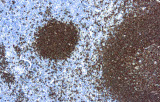

- Linfoma follicolare: tipici pattern di co-espressione (es. CD10 con BCL2 aberrante).